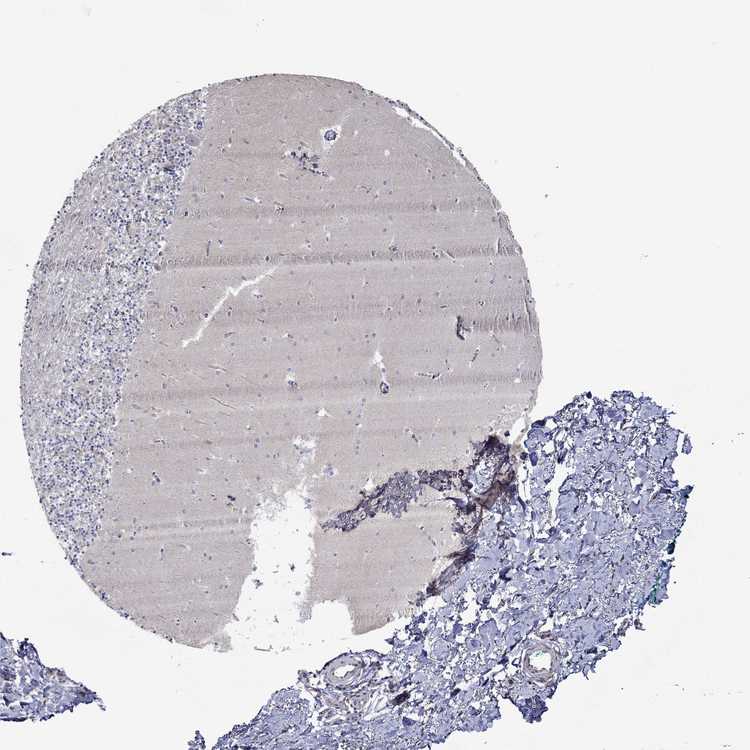

CEREBELLUM - Antibody stainingi

Antibody staining in the annotated cell types in the current human tissue is reported as not detected, low, medium, or high, based on conventional immunohistochemistry profiling in selected tissues. This score is based on the combination of the staining intensity and fraction of stained cells.

Each image is clickable and will lead to virtual microscopy that enables deeper exploration of all samples and also displays staining intensity scores, fraction scores and subcellular localization as well as patient and tissue information for each sample.

Antibody HPA076667

Purkinje cells Medium

Cells in granular layer Not detected

Cells in molecular layer Not detected